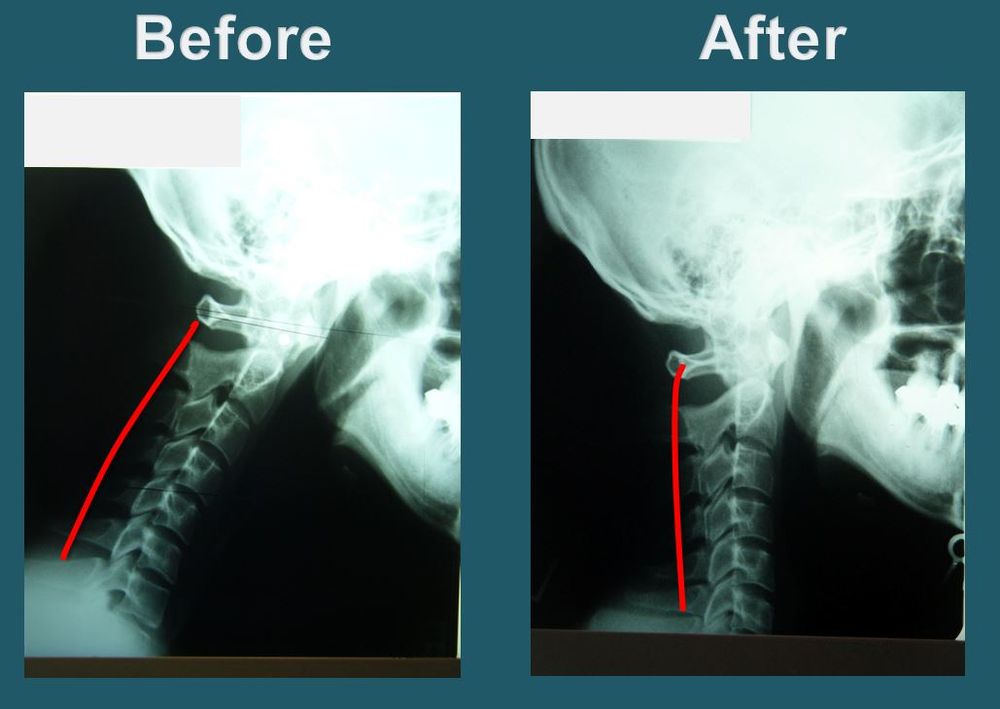

Side-scroll through X-rays captured before and after treatment.